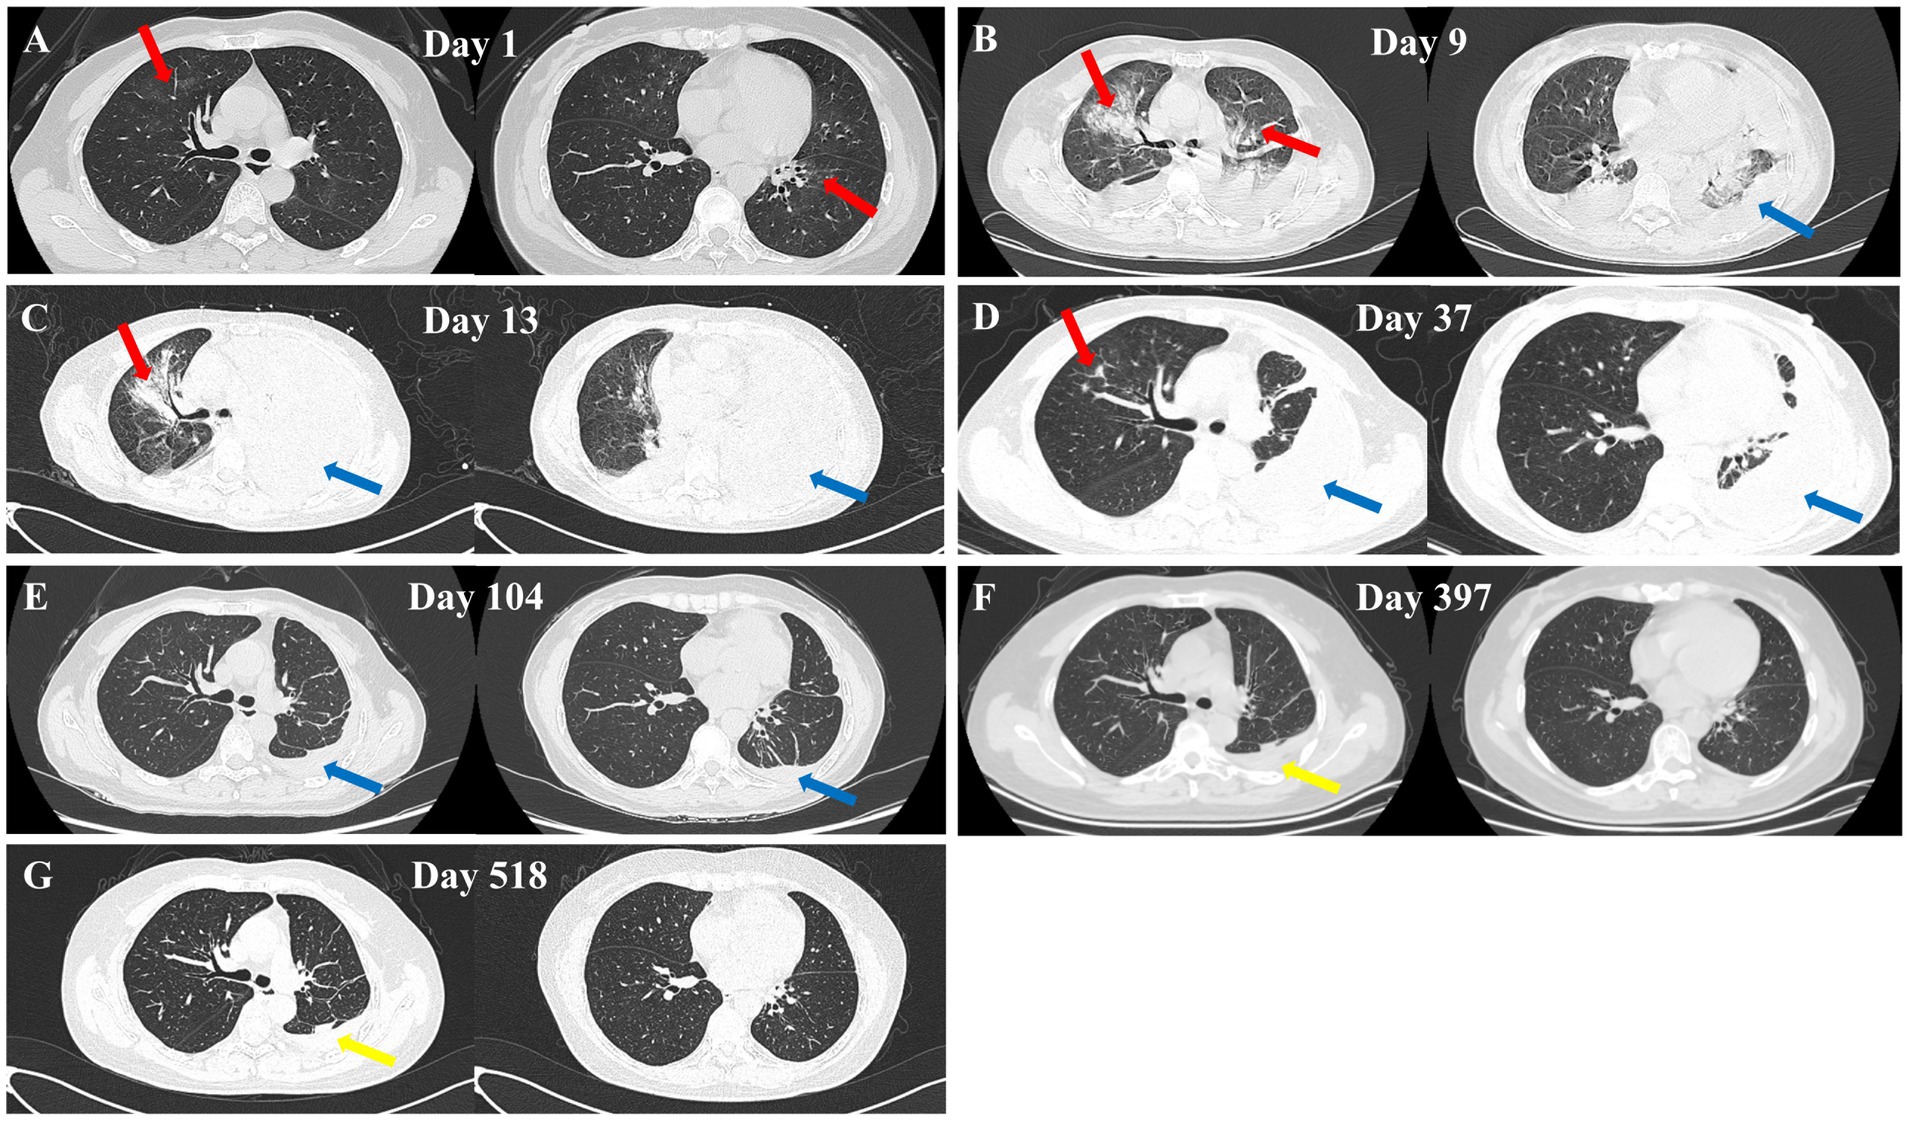

Figure 1

Chest CT images of the patient at different dates. (A) February 7, 2024 – scattered bilateral pulmonary infections (red arrows). (B) February 15, 2024 – multiple bilateral inflammatory lesions (red arrows) and pleural effusion (blue arrows). (C) February 19, 2024 – right lung inflammation (red arrow) and left lung pleural effusion with atelectasis (blue arrows). (D) March 15, 2024 – mild right lung inflammation (red arrow) and left lung pleural effusion with atelectasis (blue arrows). (E) May 21, 2024 – small amount of left-sided pleural effusion (blue arrows). (F) March 11, 2025 – left pleural thickening (yellow arrow). (G) July 9, 2025 – left pleural thickening (yellow arrow).

A 55-year-old female farmer was admitted to a local hospital on February 7, 2024, due to sudden massive hemoptysis 12 h. She ceased farming over a decade ago and has not engaged in any work involving contact with soil, humus, or organic waste in recent times. She denied recent travel history, keeping pets, or visiting epidemic areas. She reported no history of smoking or alcohol consumption and no record of immunosuppressant use. Additionally, she had no significant past medical history of chronic obstructive pulmonary disease, asthma, hypertension, diabetes, or other major conditions. Chest CT on the day of presentation revealed localized bronchial dilation in the left lower lobe with scattered infections in both lungs (Figure 1A). On February 8, 2024, the complete blood count showed a white blood cell count (WBC) of 12.57 × 109/L (reference range: 3.5–9.5 × 109/L), neutrophil count of 10.5 × 109/L (reference range: 1.8–6.3 × 109/L), neutrophil percentage of 83.60%(reference range: 40–75%), red blood cell count (RBC) of 4.08 × 1012/L(reference range: 3.8–5.1 × 1012/L) (Table 1; Figure 2A). Preliminary diagnosis: bronchiectasis with hemoptysis. The patient received conservative management but it did not resolve the symptoms, and thus, bronchial artery embolization was conducted on February 11, 2024. Subsequently, post-procedure hemoptysis resolved, however, the patient still presented with worsening symptoms of cough, chest pain, and dyspnea, accompanied by low-grade fever. A repeat CT was performed on February 15, 2024 uncovered marked disease progression characterized by bilateral patchy consolidations and pleural effusions (Figure 1B). By February 19, 2024, the patient presented with altered mental status and was transferred to the ICU of The First Affiliated Hospital of Anhui University of Chinese Medicine.

Based on the patient’s clinical presentation, imaging findings, and mNGS results, a definitive diagnosis of pulmonary Nocardia infection was established. Starting February 22, 2024, the patient’s antimicrobial regimen was adjusted to: intravenous meropenem 1 g q8h for 12 consecutive days; oral sulfamethoxazole-trimethoprim (SMZ-TMP) 0.96 g tid for a total treatment duration of 6 months; Linezolid was initially administered intravenously at 0.6 g q12h for 15 days, followed by oral administration at 0.6 g q12h until the completion of the overall antimicrobial therapy regimen (total duration: 6 months). During the patient’s hospitalization, repeated monitoring of WBC, neutrophil count, and CRP showed gradual decreases in values with treatment (Figures 2A,C). On March 15, 2024, a follow-up chest CT revealed significant resolution of right lung lesions and a left-sided encapsulated pleural effusion (Figure 1D). To promote fluid absorption, a repeat thoracentesis was performed on March 16, 2024, with intermittent intrapleural administration of urokinase (100,000 IU per session, totaling 10 sessions). The patient was discharged on March 29, 2024, with recommendations for regular follow-up examinations. The entire treatment course was illustrated in Figure 3.

During follow-up, a chest CT scan on May 21, 2024 showed complete resolution of the right-sided lesion, with only minimal residual pleural effusion on the left side (Figure 1E). A follow-up chest CT on March 11, 2025 demonstrated complete resolution of the pleural effusion and left-sided pleural thickening (Figure 1F). A follow-up chest CT on July 9, 2025, showed no significant changes compared to the previous scan (Figure 1G). The patient reported no symptoms such as coughing or sputum production. Clinically, the patient has met the criteria for cure.